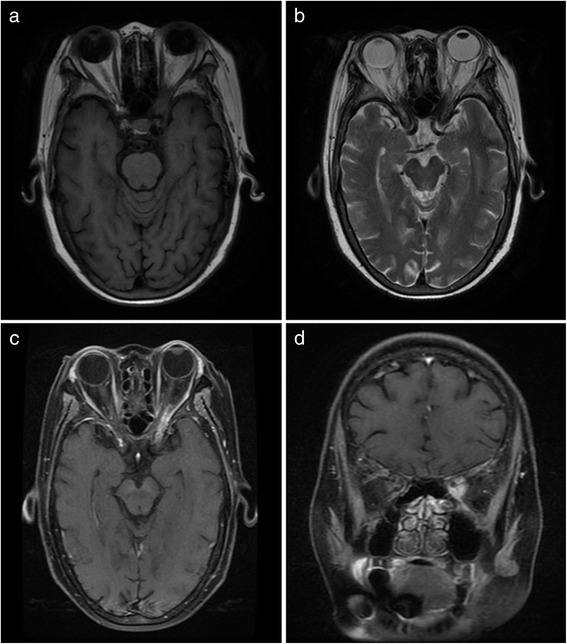

All the patients underwent CT/MRI scan of the paranasal sinuses, orbit and craniocerebrum. Pansinusitis was found in eight patients, and maxilloethmoidal sinusitis was found in three patients. The thickening sinus mucosa and extension of lesions to the orbits were observed in all patients. Four patients presented with thrombosis of cavernous sinuses. Extensionto frontal lobes, dilatation of the ventricular system and cortical grooves, and thrombophlebitis of the right lateral sinus were observed in one patient each. MRI performed in one patient revealed lesion predominantly located in sphenoid sinus, involving the left orbital apex (Fig. 2).

Fig. 2.

MRI presentations of mucormycosis presented with orbital apex syndrome. a: Axial T1WI MR shows a isointensity lesion in the left orbital apex;b: Axial T2WI MR shows a hypointensity lesion in the left orbital apex and high signal in the sphenoid sinus; c: Axial contrast-enhanced T1WI MR shows a enhancing lesion in the left orbital apex; d: Coronal contrast-enhanced T1WI MR shows a enhancing lesion in the left orbital apex